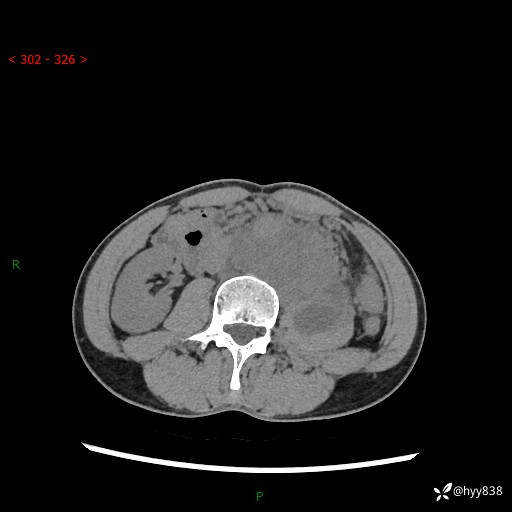

简要病史:患者无明显诱因出现左侧下腹及左侧腰背部疼痛,为间歇性隐痛,我院行胃肠镜检查,提示慢性非萎缩性胃炎,予以口服药物治疗,效果欠佳,后仍觉腹痛不适,遂至当地中医医院就诊,行彩超提示左肾积水及左肾实质性占位,遂来我院泌尿外科就诊

腹部CT平扫+增强